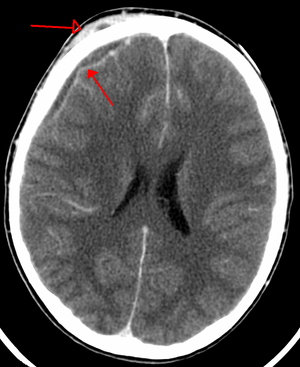

| An abscess that has led to an intracranial subdural empyema as seen on CT | |

Bacterial or occasionally fungal infection of the skull bones or air sinuses can spread to the subdural space, producing a subdural empyema. The underlying arachnoid and subarachnoid spaces are usually unaffected, but a large subdural empyema may produce a mass effect. Further, a thrombophlebitis may develop in the bridging veins that cross the subdural space, resulting in venous occlusion and infarction of the brain. With treatment, including surgical drainage, resolution of the empyema occurs from the dural side, and, if it is complete, a thickened dura may be the only residual finding. Symptoms include those referable to the source of the infection. In addition, most patients are febrile, with headache and neck stiffness, and, if untreated, may develop focal neurologic signs, lethargy, and coma. The CSF profile is similar to that seen in brain abscesses, because both are parameningeal infectious processes. If diagnosis and treatment are prompt, complete recovery is usual.